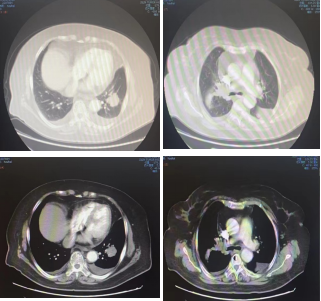

影像学-增强CT检查:右肺上叶中心型肺癌伴阻塞性肺炎,左肺下叶占位性病变,长径:2.9cm;纵隔及双肺门淋巴结转移,较大位于7组,短径1.1cm,肝脏多发点状异常密度影,考虑转移,多发骨转移。

CT检查——基线

影像学-增强CT检查:治疗4周期后,病灶缩小31%,疗效评估为PR。

靶病灶:左肺病灶明显缩小;

非靶病灶:右肺门病变缩小。

CT检查——治疗4周期后

治疗9周期后,病灶增大30%,疗效评估为PD。

靶病灶:左肺病灶增大;

非靶病灶:右肺门较前相仿。

CT检查——治疗9周期后